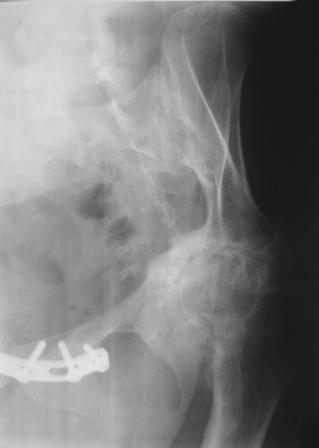

Получила травму в феврале 2004г в г.Лобытнанги ЯНАО Тюм.обл. Через неделю после поступления выполнен остеосинтез лонного сочленения пластиной. 1,5 месяца на скелетном вытяжении. В последующем ходит при помощи костылей с нагрузкой на правую ногу. Имеется нестабильность половин таза, неправильно-консолидированный перелом левой вертлужной впадины, невропатия седалищного нерва слева. В результате невропатии седалищного нерва сформировалась эквинусная установка левой стопы, парестезии по подошвенной поверхности.

Направлена к нам для устранения патологической установки стопы и эндопротезирования левого тазобедренного сустава, также имеется миграция шурупов пластины, фиксирующей лонное сочленение.

Клинически: ходит на костылях с нагрузкой на правую ногу. Левая стопа в эквинусе. Осевая нагрузка на левую н\конечность болезненна в области левого тазобедренного сустава, при прикосновениях к подошвенной поверхности стопы у пациентки чувство зжения. В левом коленном суставе полный обьем движений, в левом тазобедренном резко ограничено отведение и ротация, укорочение левой н\конечности на 2,5 см. При полипроекционной и функциональной Р-графии выявлена нестабильность левого КПС и лонного сочленения, консолидированный в порочном положении поперечный оскольчатый перелом левой вертлужной впадины с центральным смещением головки бедра. Нами выполнена коррекция деформации левой стопы. Планируется выполнить введение 2 канюлированных илиосакральных винтов слева, реостеосинтез лонного сочленения реконструктивной пластиной, после заживления ран - тотальное эндопротезирование левого тазобедренного сустава.